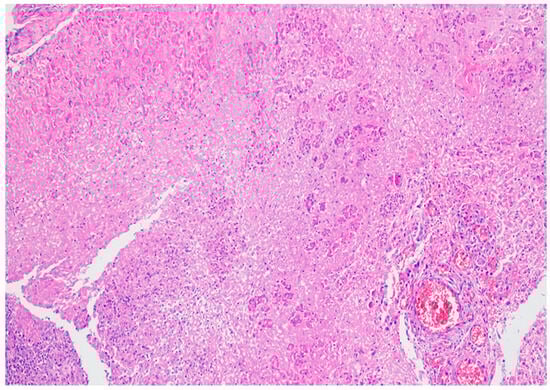

5. Histopathology of Acute Pancreatitis